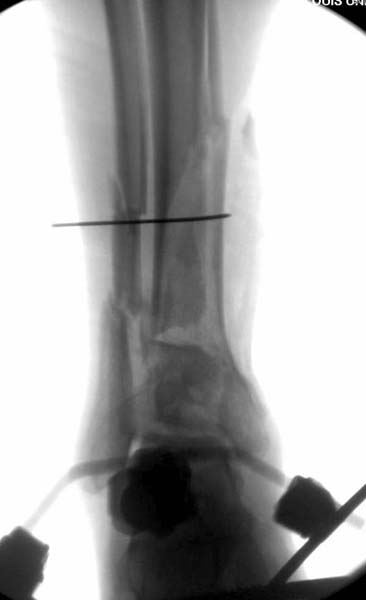

В нашем случае, травма в результате коллапса крыши. Открытый перелом. Ургентные Irrigation and Debridment, дистракция наружным фиксатором. В госпиталях первого уровня редко бывает изолированная травма, и на другой стороне повреждение стопы с переломом навикулярной кости. После обработки раны - вакуум и двухсторонние наружные фиксаторы.

Через три дня повторная I&D, где через рану манипулировали дистальным фрагментом с установкой пары межфрагментарных шурупов. На рану вакуум и следующая обработка закончилась закрытием раны. Отек держался немного дольше, чем обычно.